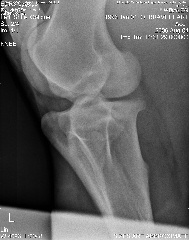

Here are the xrays from today:

Stifle oblique:

Stifle Oblique

Hi Dr. O, after reading your article, I've added the lateral view of the stifle, can you tell if you can see if he has any of the following?

osteochonDrOsis dissecans

subchondral bone cyst

osteoarthritis

Stifle Lateral view

stifle lateral

Aileen, carefully reviewing an extensive list of radiographs like you have above for any abnormality even with the original set of full sized radiographs could take up to an hour and an hour more to write about. Reviewing these tiny pictures would be of no value at all. While I don't mind looking at the occasional radiograph the above is beyond the scope of this site.

If you want a second opinion on these I strongly recommend you send them to a certified veterinary radiologist, like you find at a university veterinary school, they could tell you more than I would be able to.

Surgeon says mild to moderate djd in hocks and stifle. His stiffness is much much better, not overall anymore, so I do think the hock injections helped.